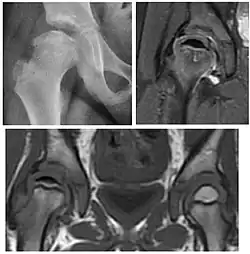

Magnetic resonance imaging

Many pathological conditions of the hip are detected early by MRI due to its high soft tissue resolution and sensitivity. Its accuracy in studying acute hip pain in children has proved to be superior to ultrasound and plan film radiography. However, MRI accessibility and the need of sedation relegate its use to selected cases in which diagnosis is not clear with less demanding techniques. These include differentiating transient synovitis from a septic arthritis or osteomyelitis, diagnosis of inflammatory joint disease or bone tumors, and early detection and follow-up of Perthes disease.[1]

MRI findings correlate with prognosis in LCPD. These include extent and distribution of epiphyseal necrosis, subchondral ossified nucleus fracture, involvement of the lateral pillar, and disturbance of physeal growth, including presence of transphyseal neovascularity or bridging.[1]

In adults, MRI is currently playing a definite role in the assessment of osteoarthritis. Although traditionally belonging to the arena of radiographs, the role of MRI has been stressed after the term femoral acetabular impingement was coined in 2003. Growing interest has been focused in accurate diagnosis of the acetabular and femoral morphological abnormalities that may lead to early osteoarthritis.[1]

MR imaging is considered paramount to these objectives, mainly when surgery is considered, due to the ability of MRI to portray the whole section of the femoral neck surface, as well as to image the labrum and articular cartilage.[1]

Most of the angles and measurements described in the plain radiograph section can be accurately reproduced on MRI. In addition, the superiority of MRI resolution with intra-articular contrast allows detection of labral and chondral abnormalities that may influence the choice of medical, percutaneous, or surgical management (Figure 9).[1]

Figure 9:

MR arthrography has proven superior in accuracy when compared to native MR imaging. It is considered the best technique to assess the labrum. Knowledge of the normal variable morphology of the labrum helps to differentiate tears from normal variants. A triangular shape is most commonly seen in 66% of asymptomatic volunteers, but round, flattened, and absent labra can also be found in asymptomatic populations. MR arthrography has demonstrated sensitivity over 90% and specificity close to 100% in detecting labral tears. Loose bodies are demonstrated as filling defects surrounded by the hyperintense gadolinium.[1]

Association between labral tears and chondral damage has been demonstrated. This underscores the interaction between cartilage and labrum damage in the progression of osteoarthritis. Chondral damage to the posteroinferior part of the acetabulum as a contrecoup lesion occurs in approximately one-third of pincer cases secondary to persistent abutment on the anterior part of the joint leading to a slight posteroinferior subluxation. This is considered a bad prognosis sign.[1]

MR arthrography can also demonstrate ligamentum teres rupture or capsular laxity, which are debated causes of microinstability of the hip. Elongation of the capsule or injury to the iliofemoral ligament or labrum may be secondary to microtrauma in athletes. MR can demonstrate abnormalities in these cases, such as increased joint volume or a ligamentum teres tear (Figure 9).[1]